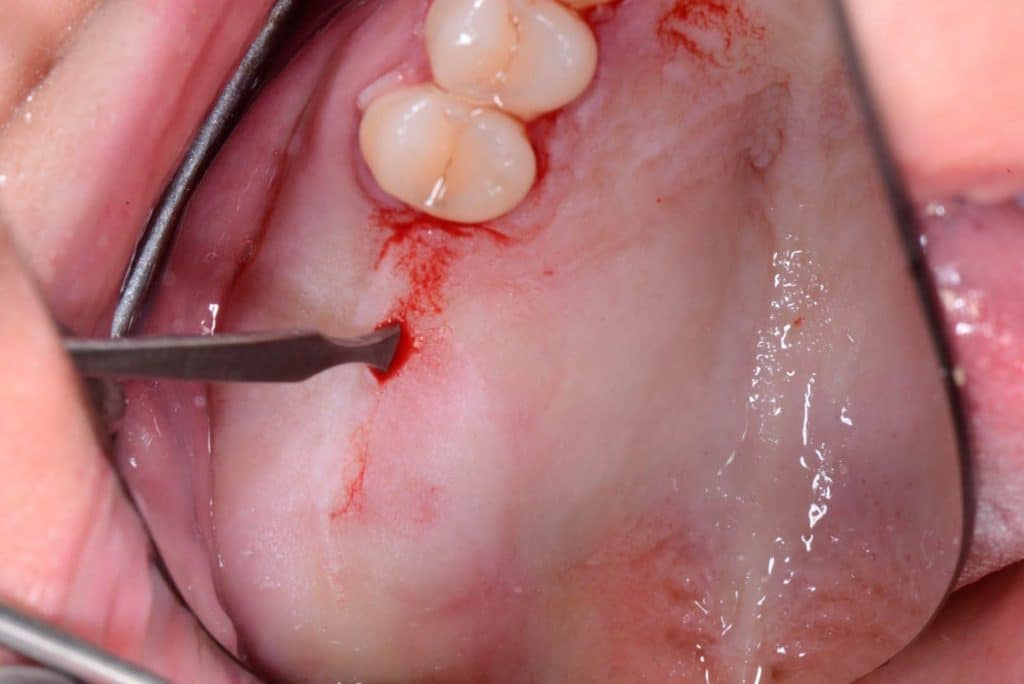

Two 8mm Straumann Wide-Neck have been inserted. After inserting a healing abutment with a height of 2 mm, a detached stitches suture was made. Good planning allowed me to be precise with the incision, and only 2 stitches have been necessary.

one week follow-up